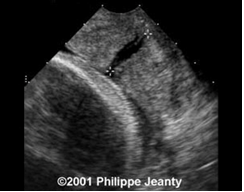

- Siêu âm bìu:

- Các bất thường của tinh hoàn như: nang mào tinh, tràn dịch tinh mạc, giãn tĩnh mạch thừng tinh, sỏi nhỏ tinh hoàn.

Thể tích tinh hoàn và giãn tĩnh mạch thừng tinh

Biểu đồ 2. Thể tích tinh hoàn và giãn tĩnh mạch thừng tinh

Thể tích tinh hoàn ở các bệnh nhân bị giãn tĩnh mạch thừng tinh nhỏ hơn một cách đáng kể so với các bệnh nhân không có giãn tĩnh mạch thừng tinh (p≤0,001).